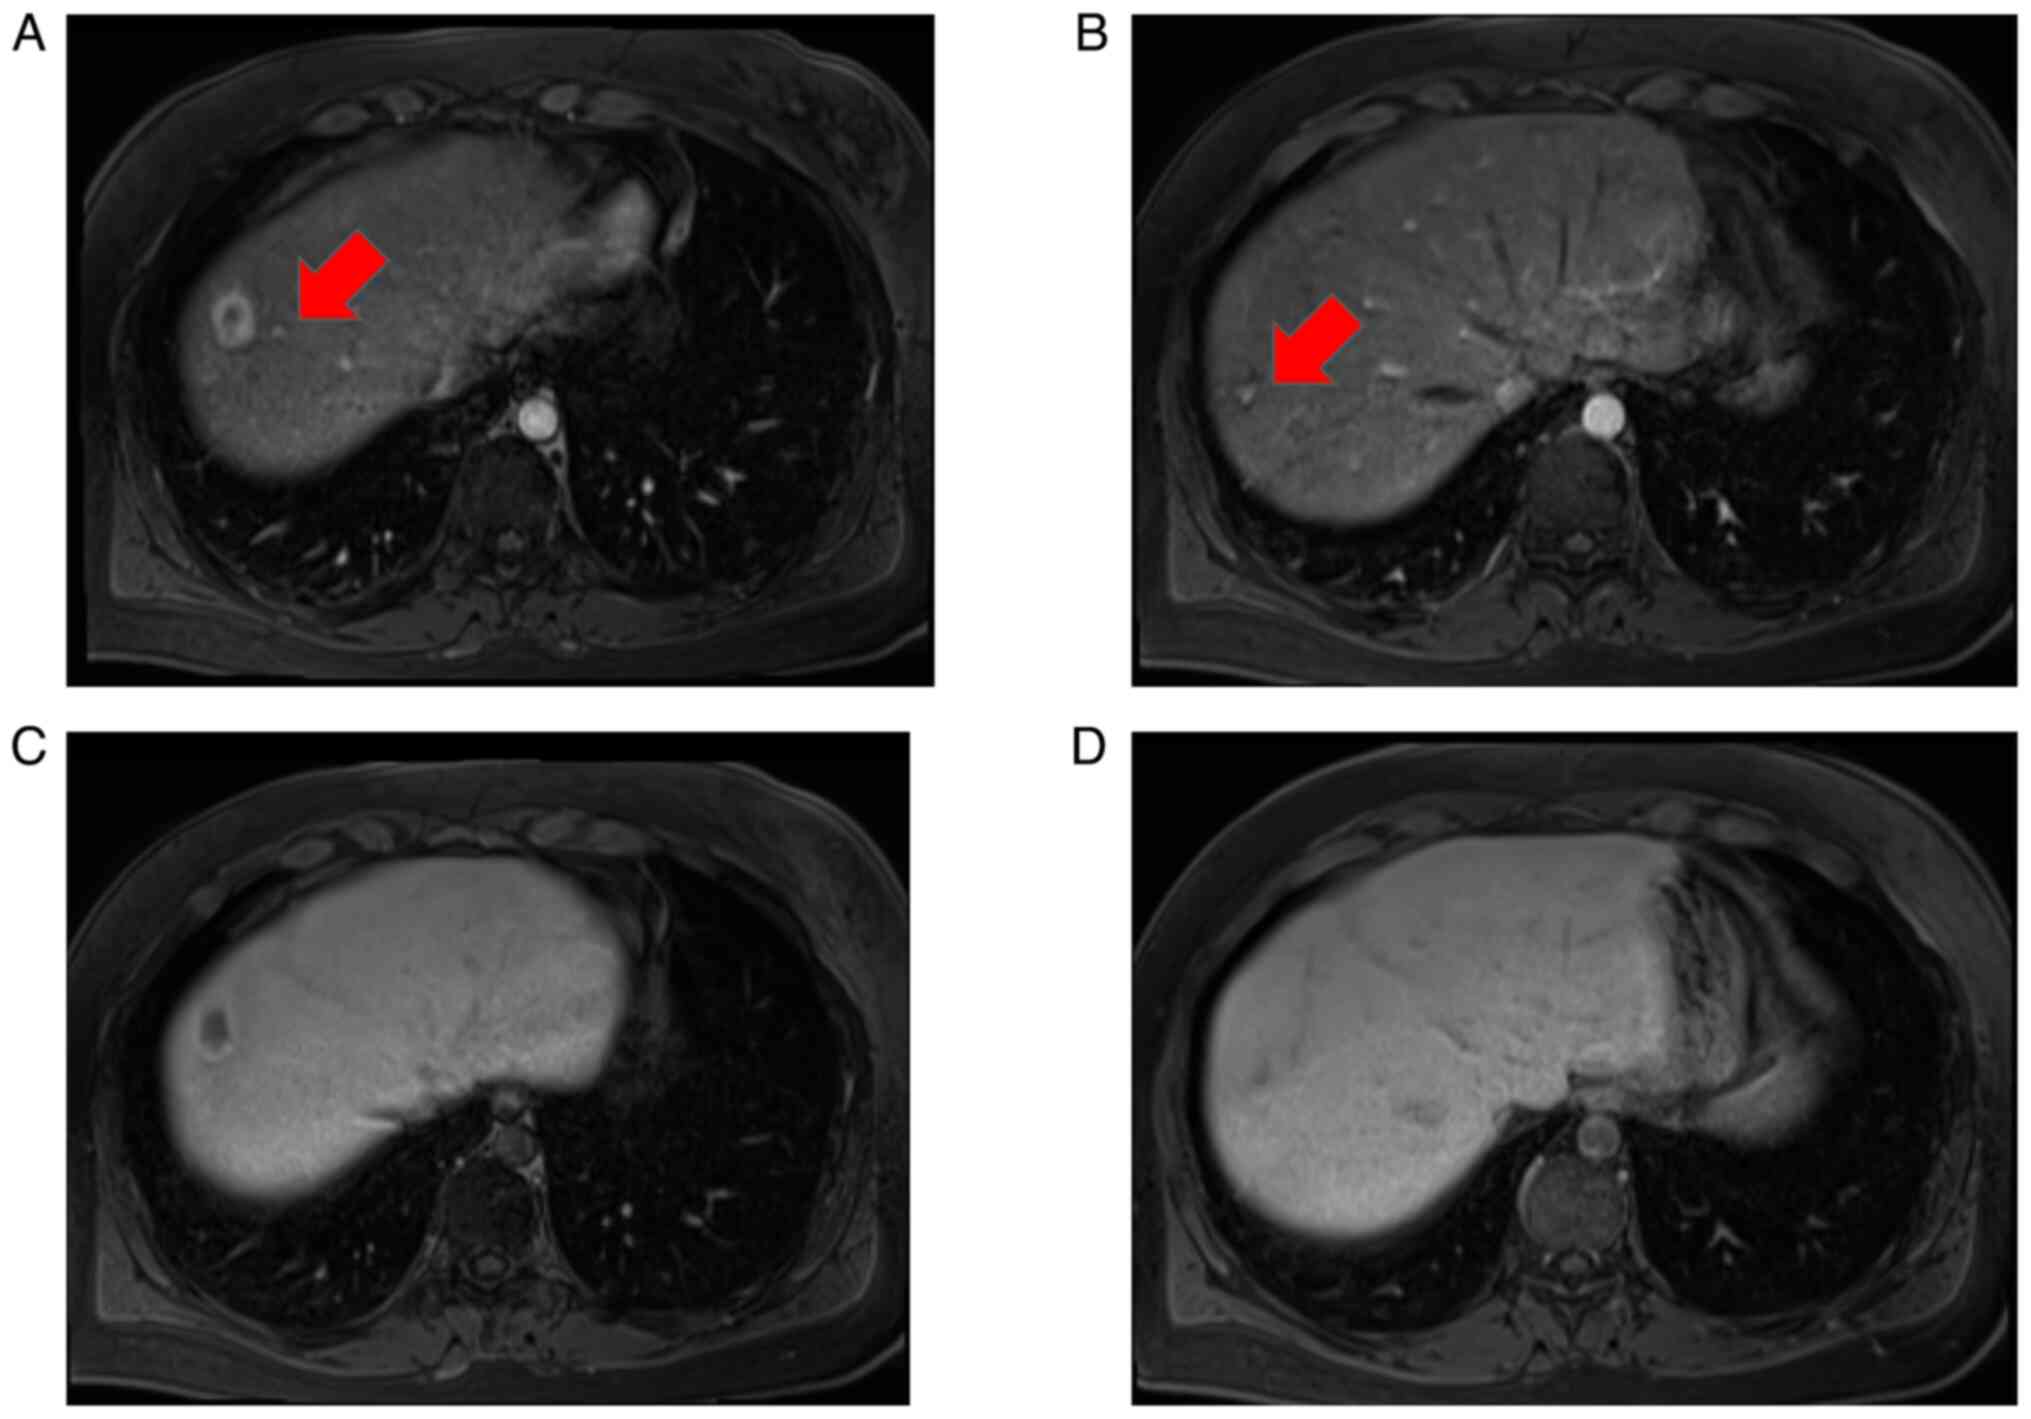

Ultrasonography revealed multiple hyperechoic tumors in the liver (Fig. 1A-C). Magnetic resonance imaging (MRI) was performed before a dynamic computed tomography (CT) scan to limit radiation exposure (8,12). MRI examinations were performed using 1.5-T MR systems (MAGNETOM Sola, Siemens Medical Solutions, Erlangen, Germany). The gradient strengths were 45mT/m with a slew rate of 200T/m/second. Eighteen-element phased array matrix coil was used for signal reception. MRI showed that the main tumor in segment (S)8 had low signal intensity on both T1- and T2-weighted images and slightly high signal intensity on diffusion-weighted imaging (Fig. 2A-C). Contrast-enhanced MRI revealed that the S8 tumor was enhanced in a ring shape during the early contrast phase (Fig. 2D). In the hepatobiliary phase, the periphery had a high signal intensity and the interior had a low signal intensity (Fig. 2E). Near the main tumor in S8, two small tumors were heavily contrasted in the early phase but were not identified in the hepatobiliary phase (Fig. 3). Numerous tumors suspected to be lipomas, focal nodular hyperplasia or arterio-portal shunts were also observed in the liver.

Figure 2

MRI findings of primary tumor. MRI showed that the primary tumor in S8 had a low signal in (A) T1 and (B) T2 (arrow). (C) Primary tumor in S8 had a slightly high signal in diffusion-weighted images (arrow). (D) On contrast-enhanced MRI, the primary tumor in S8 was enhanced in a ring shape in the early contrast phase (arrow). (E) In the hepatobiliary phase, the periphery of the tumor had a high signal and the interior had a low signal (arrow). S8, segment 8.

Figure 3

MRI findings of two small tumors. On (A) left and (B) dorsal side near the primary tumor in S8, a small tumor was observed that were heavily contrasted in the early phase (arrow). (C) Small tumor on the (C) left and (D) dorsal side near the main tumor could not be identified in the hepatocellular phase. S8, segment 8.